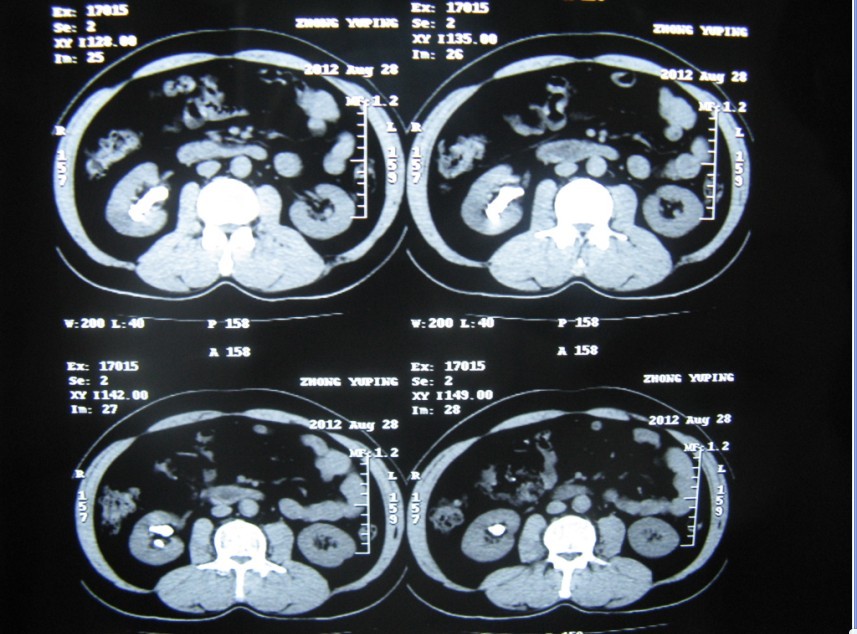

患者鐘某主因“右側(cè)腰部間斷疼痛20余年加重3個(gè)月”入院。如下圖圖1、圖2和圖3所見(jiàn)具備兩個(gè)特點(diǎn):一、結(jié)石復(fù)雜,除主體位于腎盂和中下大盞外,多個(gè)中下小盞內(nèi)還有多發(fā)結(jié)石;二、沒(méi)有腎積水,腎盞杯口不大。

3 術(shù)前CT片可以看到結(jié)石位于右腎盂及中下各盞,無(wú)腎積水